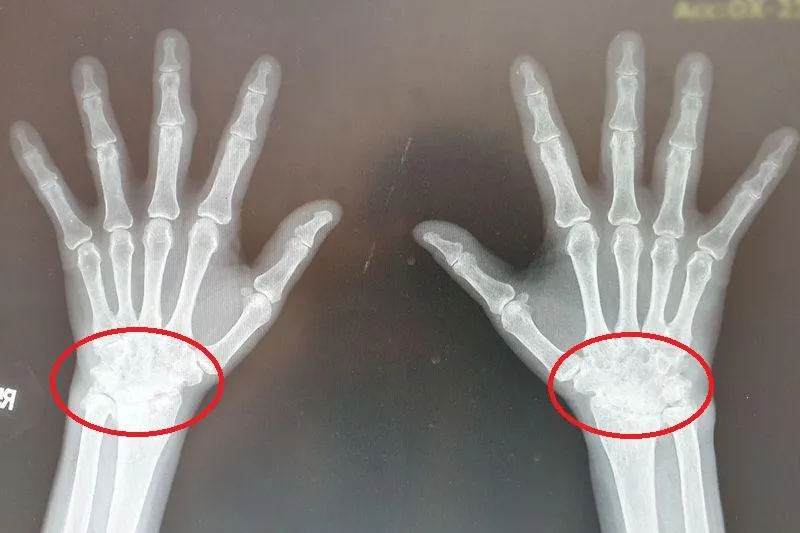

類風濕性關節炎

關節疼痛

過敏免疫風濕科

黃柏豪

關節損壞

類風濕關節炎

生物製劑

發炎指數

關節

骨侵蝕